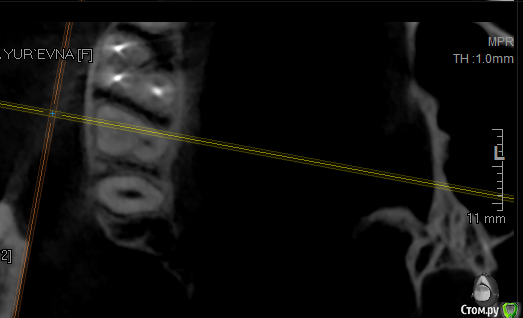

krokomot Опубликовано 17 октября, 2019 Поделиться Опубликовано 17 октября, 2019 Проблема в фуркации шёчных каналов, есть расширение щели и сниженный показатель денситометрии кости прилегающей к этому участку, в отличие от других участков, это означает что кость там находится в процессе атрофии. Ссылка на комментарий

vse32 Опубликовано 18 октября, 2019 Автор Поделиться Опубликовано 18 октября, 2019 Проблема в фуркации шёчных каналов, есть расширение щели и сниженный показатель денситометрии кости прилегающей к этому участку, в отличие от других участков, это означает что кость там находится в процессе атрофии.Самая привлекательная для меня версия. Считаете проблема в бифуркации? Ссылка на комментарий

krokomot Опубликовано 18 октября, 2019 Поделиться Опубликовано 18 октября, 2019 По кт пломбировку каналов и состояние корней судить нельзя, только опосредовано через состояние периодонтальной щели и костной ткани, это относительно достоверные признаки, при трещине или переломе мы не увидим трещину корня, но увидим измененя косиной ткани. В данной ситуации по кт сомнительную зону я обнаруживаю только в области фуркации щечных каналов, и то я вления не выраженные, хотя длительный процесс более месяца обязан был дать четкую картину на кт, но ее нет. Была у меня такая пациентка с периодонтитом переднего зуба, болел полгода, никаких рентегологических признаков указывающих на периодонтит небыло, вскрытие показало канал пустой. Ссылка на комментарий

___49___ Опубликовано 18 октября, 2019 Поделиться Опубликовано 18 октября, 2019 устье плохо визуализируется , больше ориентируюсь на анатомию корня , два скрина с отметкой и без . Ссылка на комментарий

___49___ Опубликовано 18 октября, 2019 Поделиться Опубликовано 18 октября, 2019 еще 2 скрина также с меткой и без , где четко виден канал мб2 Ссылка на комментарий